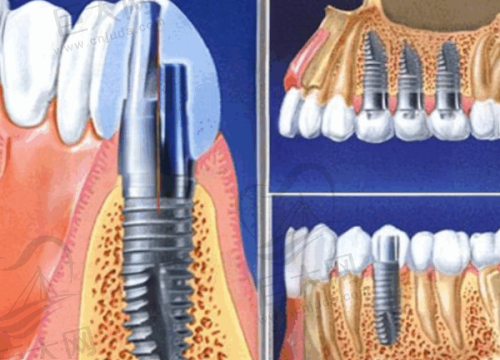

临汾完美齿科注重个性化服务与新型技术的结合。它拥有一支团队,能够为患者提供从常规检查到复杂治疗的多方位服务。这里特别重视患者的舒适体验,医生会根据每位患者的情况进行个性化服务。虽然其室内面积并不大,总共有两层,但医用设备和技术不用担心。张建国作为临汾完美齿科的院长,到现在为止已有14年的工作经验,尤其是在种植牙项目上积累了丰富的治疗技巧。比如在操作过程中,他会根据牙齿的缺失数量、健康状态、以及骨质、骨量、骨密度等多方面因素综合考虑,然后配合相应的治疗。